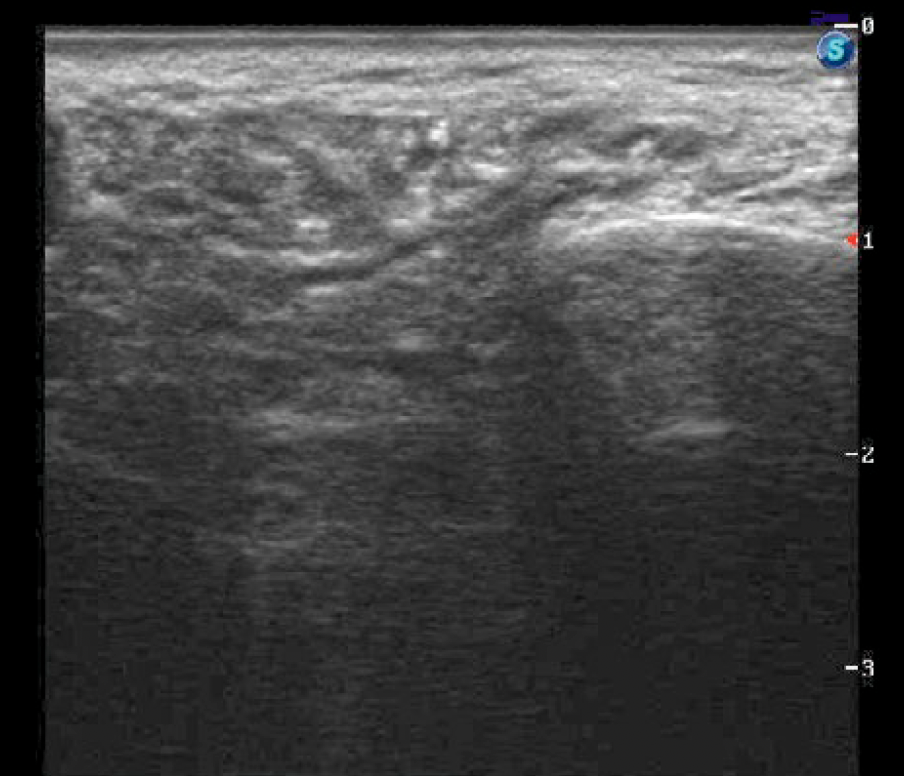

В контрольной группе этот показатель составляет в левой и правой ПСЖ по 4,2 и 5% соответственно, медиана расширения протока составила 0,5 мм [0,3—0,6] при максимальном расширении до 0,8 мм (рис. 2).

При сравнении степени расширения протоковой системы было отмечено более значительное расширение протоковой системы у пациентов после РЙТ в основной группе (p=0,003).

Поэтому клинически мы наблюдаем сухость в полости рта, вызванную уменьшением количества слюны и застоем ее изза образования стенозов и стриктур в протоковой системе, которые уже компенсаторно способствуют образованию расширений протоков, визуализируемых с помощью УЗ-диагностики.

Таким образом, снижение эхогенности, появление неоднородности структуры, особенно ОСЖ, и расширение протоковой системы >0,8 мм являются значимыми УЗ-паттернами развития сиаладенита после РЙТ.